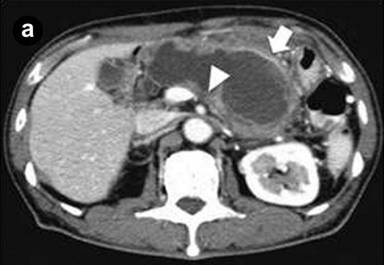

A 75-year-old man was admitted to the hospital because of acute onset of severe epigastric pain and body weight loss. On physical examination, palpable mass and tenderness of upper abdomen was noted. Laboratory studies revealed elevated C-reactive protein (7.0 mg/dL; reference range: 0-0.5 mg/dL), CEA (39.7 ng/mL; reference range: 0-5 ng/mL), CA 19-9 (62.3 U/mL; reference range: 0-37 U/mL) and HbA1c (13.2%; reference range: 3.4-5.8%). Results of complete blood count, plasma levels of electrolytes, tests of coagulation, amylase, lipase, kidney and liver function were within normal limits. Computed tomography (CT) and magnetic resonance imaging (MRI) of the abdomen showed a markedly dilated main pancreatic duct (45 mm), a papillary tumor (20 mm in diameter) protruding into the main pancreatic duct of the distal pancreas and splenic vein obstruction (Figure 1abc). On duodenoscopy with a lateral viewing of endoscope, mucus was discharged from the enlarged papilla of Vater (Figure 2a). Peroral pancreatoscopy was performed, revealing the papillary tumor on the main pancreatic duct (Figure 2b). Pathological examination of biopsy specimens of the tumor showed papillary mucinous adenoma (Figure 2c).

Figure1. a. Computed tomography (CT) showed a markedly dilated main pancreatic duct (45 mm, arrow) and splenic vein obstruction (arrowhead). b. CT showed a papillary tumor (20 mm in diameter) protruding into the main pancreatic duct of the distal pancreas (arrowhead). c. Magnetic resonance cholangiopancreatography (MRCP) showed a markedly dilated main pancreatic duct. |